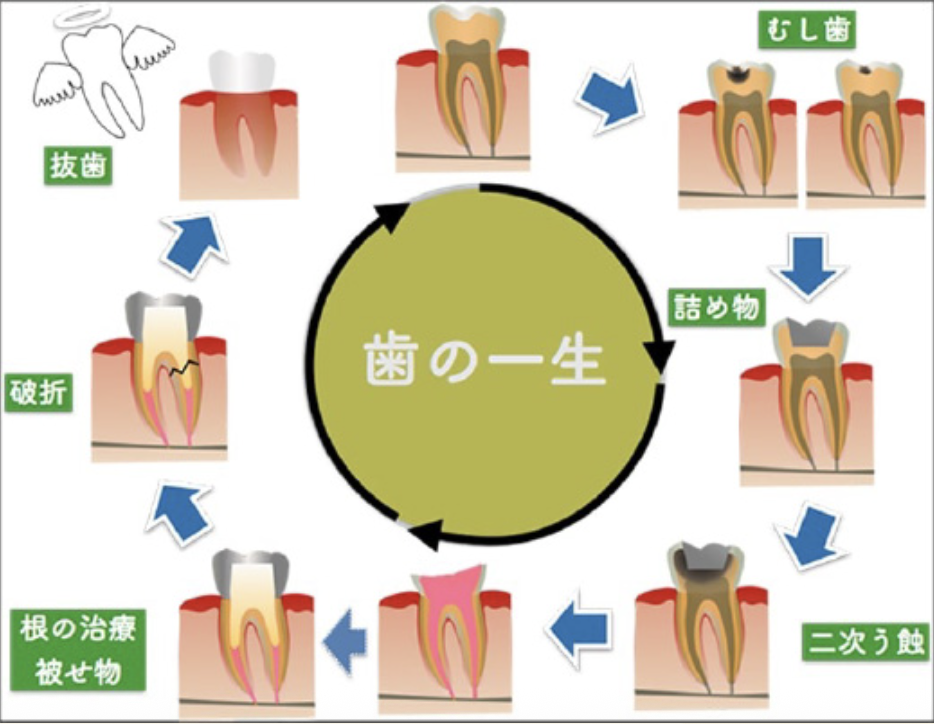

私たちの歯は、毎日の食事や会話、笑顔に欠かせないとても大切な存在です。でも、そんな歯にも「一生」があります。

多くの歯は、小さな虫歯からそのストーリーが始まります。

最初は、白い樹脂(コンポジットレジン)で詰めるだけの小さな治療で済みますが、それをきっかけに、再治療のサイクルが始まってしまうこともあります。

虫歯は再発を繰り返すほど歯を削る量が増え、神経を取る治療や最終的には抜歯に至る可能性が高まります。平均して同じ歯を6〜7回治療すると抜歯のリスクが高いとされており、歯は一度削ると元に戻りません。そのため当院では、「一度の治療でできるだけ長く歯をもたせること」を重視しています。材料には寿命の差があり、患者さまの状態やライフスタイルに合わせて選択が可能です。今だけでなく10年、20年先を見据え、神経を残し、自分の歯を守る治療を丁寧な説明とともに行っています。